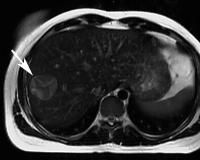

Echinokokkus - Leber

Abbildung 1

Echinococcus granulosus

,

Hepatologie

Leber

Magnetresonanztomographie